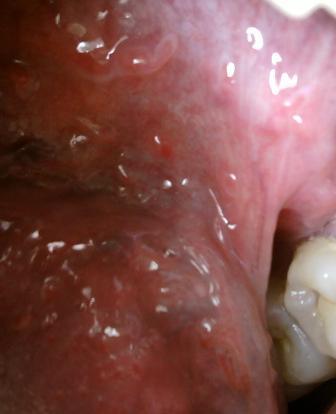

警惕尖锐湿疣病毒交叉感染尖锐湿疣具有很强的传染性,主要有以下三种途径:直接接触传染,间接接触传染和母婴传染。早期病情是比较轻微的,不及时治疗,严重危害人体健康,害人害已,会把病毒传染给身边的亲人。临床上常用的治疗尖锐湿疣方法是;:激光疗法,微波疗法,电灼疗法,冷冻疗法好手术疗法等等,尖锐湿疣久治不愈,对于人体健康带来的危害将会是比较大的,因此建议大家在患病之后应该及时去专业的医院进行治疗。